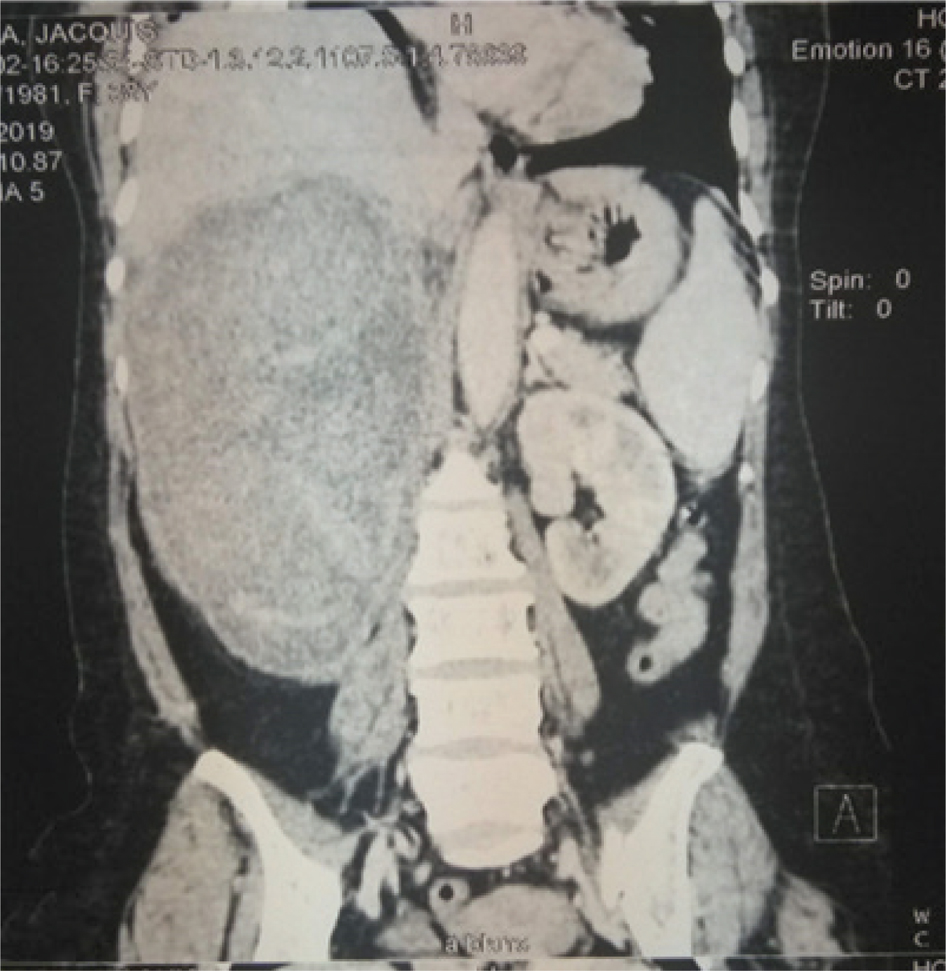

History and physical exam are important components of assessing a renal mass. The relevant clinical presentation including hematuria, flank pain, and lumbar mass should be ascertained. All possible risk factors or etiologies should be sought. Physical exam findings of varicocele or pedal edema could depict vascular involvement of the tumor or inferior vena cava (IVC) invasion. Though most authors reported the clinical triad of RCC, the presence of a lumbar mass was reported in all the studies reviewed from the sub-Saharan region (1020). A complete blood count (CBC), renal function (creatinine, estimated glomerular filtration rate), liver function (alanine transaminase, aspartate aminotransferase), and bony markers (alkaline phosphatase, calcium) should be evaluated (1, 9). In the presence of an elevated creatinine, a renal scintigraphy should be performed to assess renal function. Computed tomographic scan (CT-scan) is the imaging of choice with about 90% accuracy for renal masses (Figures 1 and 2). Renal malignancy is most likely when contrast attenuation of 10–20 Hounsfield Unit (HU) is obtained for a renal mass (9). CT scan is essential for staging renal cancer, lymph node assessment, as well as identification of metastasis. A chest CT is ideal for assessing metastasis when findings of chest x-ray are equivocal. Magnetic resonance imaging (MRI) and Doppler ultrasound are useful for determining the IVC involvement. Findings by Tengue et al., Tijani et al., Avokoudjo et al. and Salako et al. highlighted the use of CT-scan and ultrasound to diagnose and stage renal malignancies. The use of intravenous urogram (IVU) though limited was reported by some studies (12, 15, 19, 20) from the sub-Saharan region. It may have been useful for large tumors that may have distorted the renal parenchyma.

Fig 1

Figure 1: A contrast coronal CT-scan showing a hyper vascularized right T4 renal tumor found to have affected the renal vein, IVC, and inferior margin of the liver.